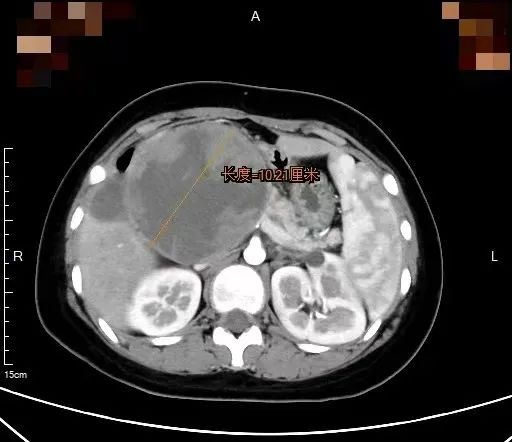

于是家人带小微来上海某三甲医院胰腺外科就诊,增强CT检查显示,一个直径10公分的肿瘤像狰狞的章鱼,触须般的包膜紧紧缠绕着小微的胰头部位,将十二指肠压成了“纸片”,消化道完全梗阻,肿瘤内部甚至出现渗血!

胰头被十二指肠环抱,后方紧贴着门静脉和肠系膜血管,巨大的肿瘤在胰头这个“交通枢纽”位置,不仅压迫胆总管、胰管,还侵蚀了十二指肠乳头,就像卡住的巨石,阻断了消化液流动,还随时可能引发致命性出血或感染。更危险的是影像上可见肿瘤内部散在的出血点,意味着巨瘤随时可能破裂,情况十分危急。